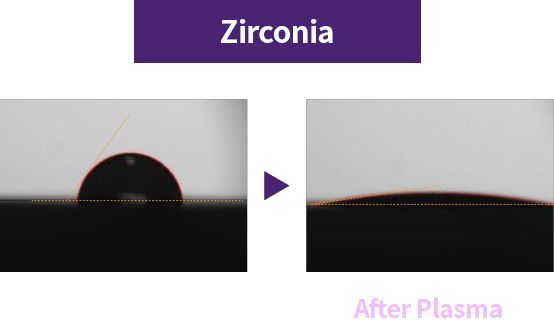

Plasma treatment improves surface hydrophilicity → promotes blood and protein adhesion → an implant the body accepts more easily

High |

Hydrophilicity |

Relatively Low |

Plasma treatment helps remove impurities left on the implant surface and improves surface hydrophilicity for better biocompatibility. Thanks to these benefits, plasma technology helps improve implant success and serves as a key factor for faster recovery.

Improved early protein attachment through organic removal and surface activation